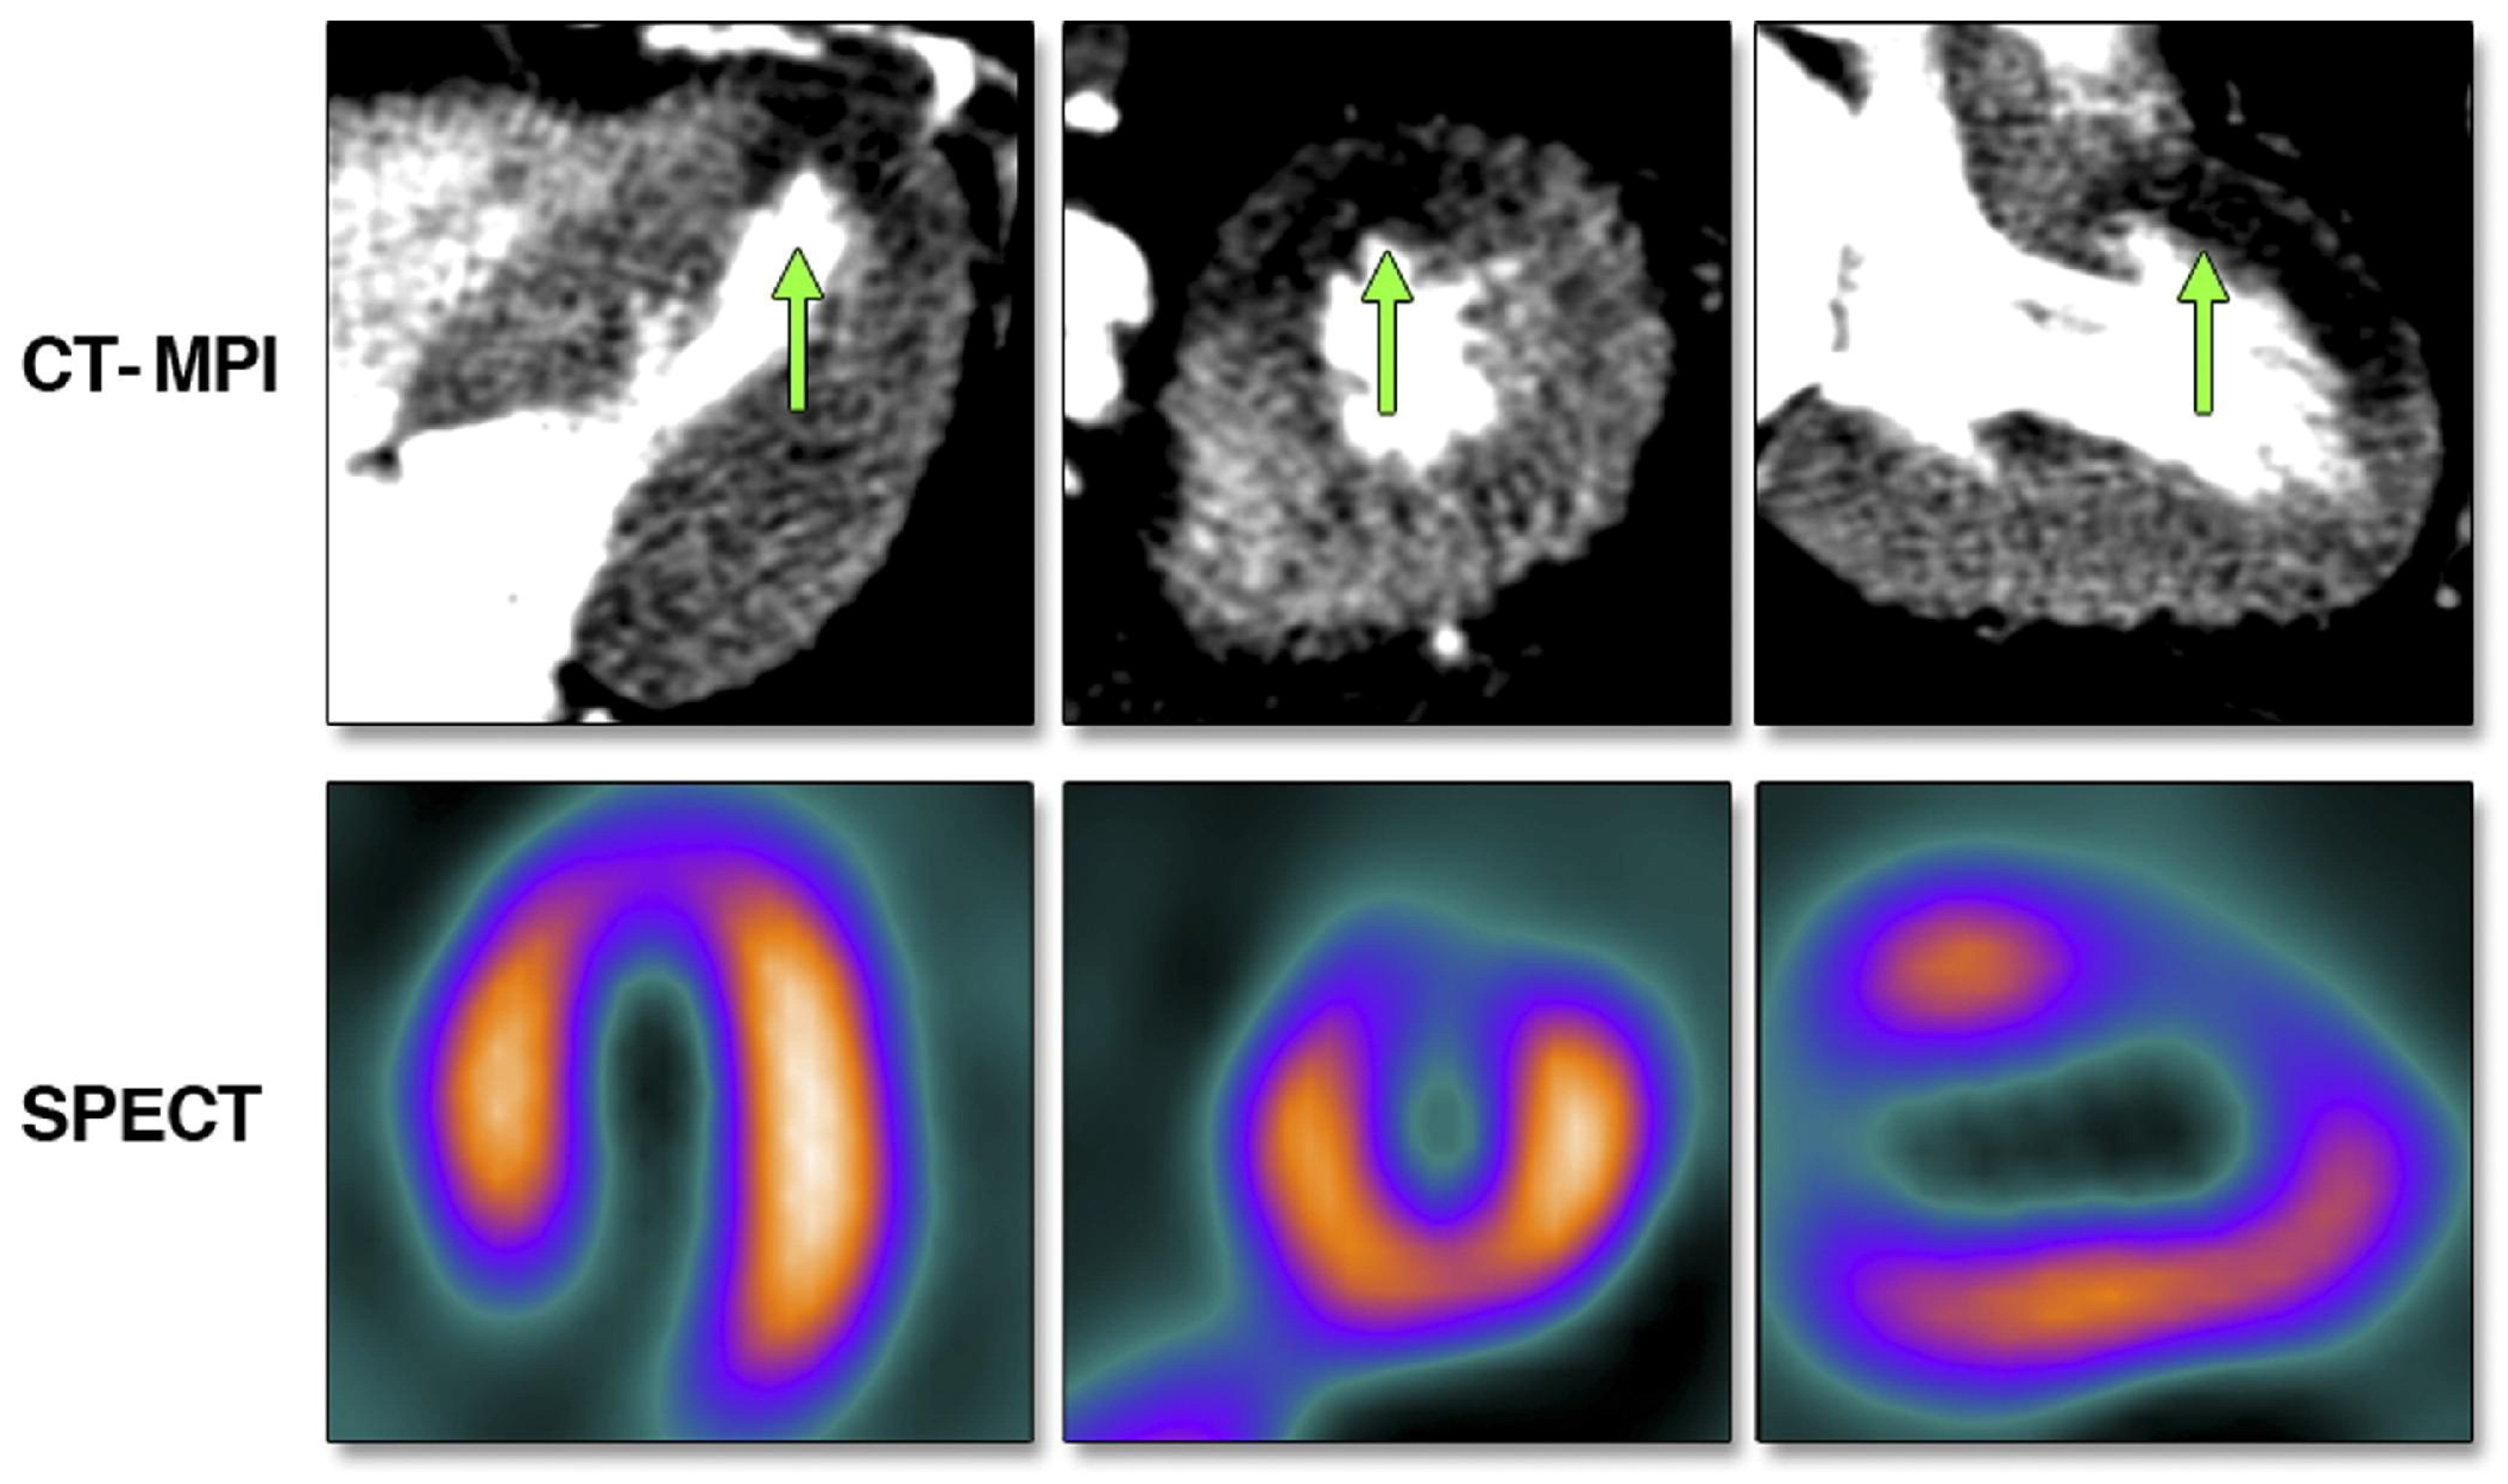

| CTP | − | + Static: qualitative evaluation of MP Dynamic: quantitative evaluation of MP Incremental hemodynamic information compared to plain CCTA, especially in multivessel disease CTP-derived MBF flow may be predictive of adverse outcomes | |